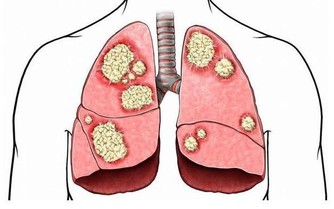

*****2.吸煙*****

吸煙會減慢腎臟供血速度,腎臟流入的血液減少,會損害腎臟的功能。有研究顯示,有20年以上家庭環境被動吸煙史與無家庭環境被動吸煙史比較,腎癌發病風險增加2.18倍。